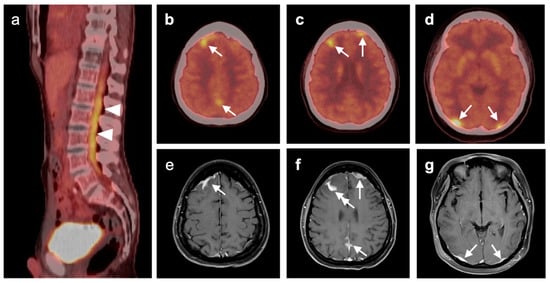

3.5. Brain Metastases

- Galldiks, N.; Langen, K.-J.; Albert, N.L.; Chamberlain, M.; Soffietti, R.; Kim, M.M.; Law, I.; Le Rhun, E.; Chang, S.; Schwarting, J.; et al. PET imaging in patients with brain metastasis-report of the RANO/PET group. Neuro-Oncology 2019, 21, 585–595. [Google Scholar] [CrossRef]